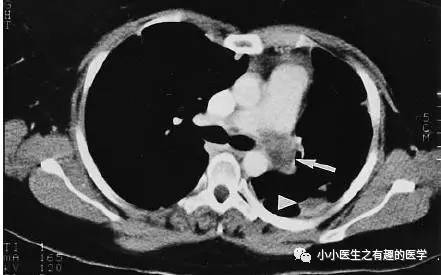

这是什么?妥妥的肺栓塞啊,还能有啥?

是的,这不是肺栓塞,这是肺动脉内膜肉瘤。这不是扯蛋肺栓塞,这是扯蛋肺动脉肿瘤。扯蛋是肯定的,然而,血栓且不肯定。

充盈缺损的地方,密度不均匀,并且,有强化,血栓里面没有血管,一般不会强化,所以,有可能是肿瘤。